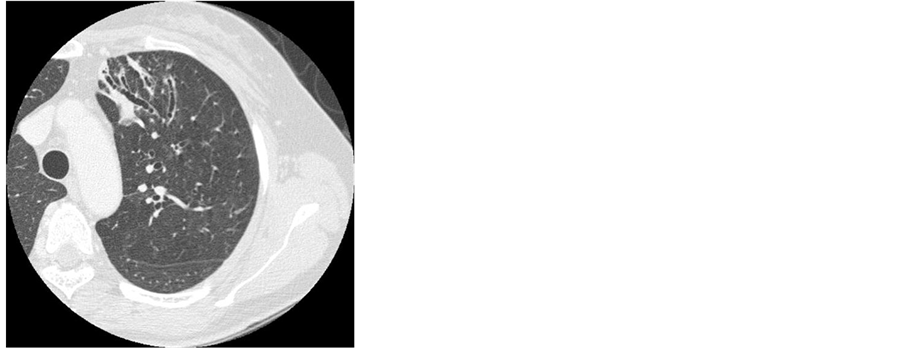

Case 1: A53-year-old woman visited our hospital due to an abnormal chest shadow. She had no underlying diseases and no smoking history. There were no abnormal physical findings on admission. There were no abnormal laboratory findings in the peripheral blood or chemical screening, but Quanti FERON TB-Gold (QFT-G) was also positive (ESAT-6: 0.92 IU/ml). Chest radiographs showed nodular and linear shadows in the left upper lung field (Figure 1). Chest CT showed nodular and linear shadows with bronchiectasis and small cavities in the left upper lobe and lingula (Figure 2). Because she could not expectorate sputum and we could not rule out pulmonary tuberculosis completely, we performed bronchoscopy. The culture of bronchoscopic specimens generated acid-fast bacilli and the result of DNA-DNA hybridization (DDH) method identified M. kansasii. Finally, she was diagnosed with pulmonary M. kansasii disease. Afterwards, she was treated with combined chemotherapy using INH, RFP, and EB for one year and abnormal chest shadows improved following the combined chemotherapy.

Figure 2. Chest CT showed nodular and linear shadows with bronchiectasis and small cavities in the left upper lobe and lingula.